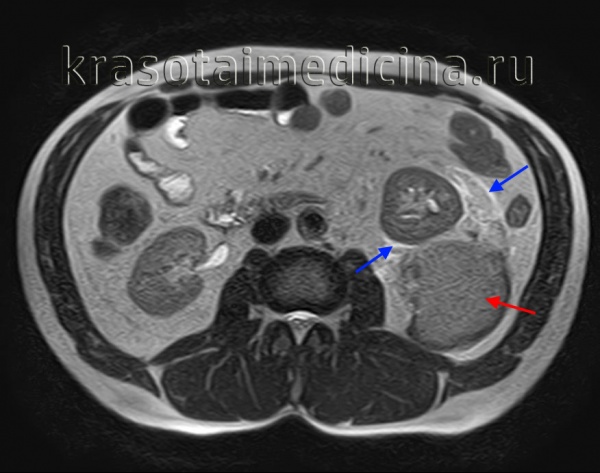

МРТ ОБП. Повреждение левой почки. Забрюшинная гематома (красная стрелка), отек перинефральной клетчатки (синяя стрелка).